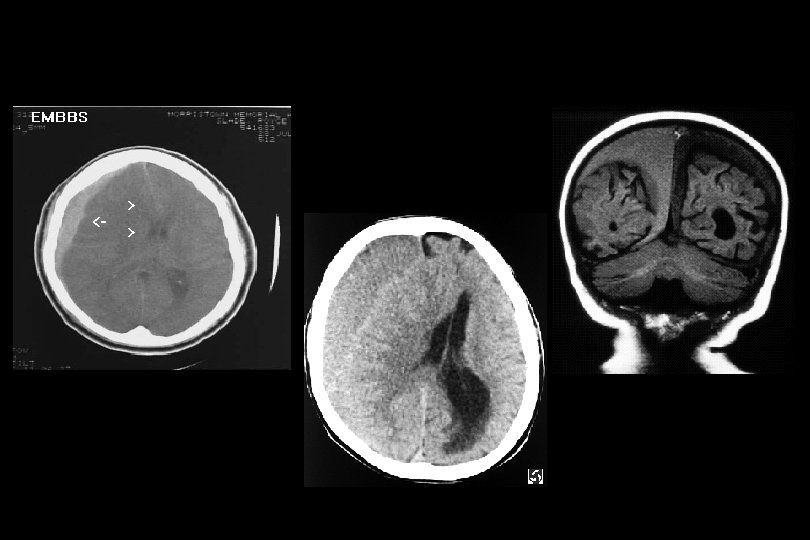

Diffüz aksonal yaralanma • koma hali • ölüm oranı % 33 -50 • derecelendirme 1. aksonal yaralanma ak cevherde, korpus kallozumda, beyin sapında ve serebellumdadır 2. ek olarak korpus kallozumda fokal lezyon var. 3. ek olarak beyin sapı rostrumunun dorsolateralinde fokal lezyon vardır.